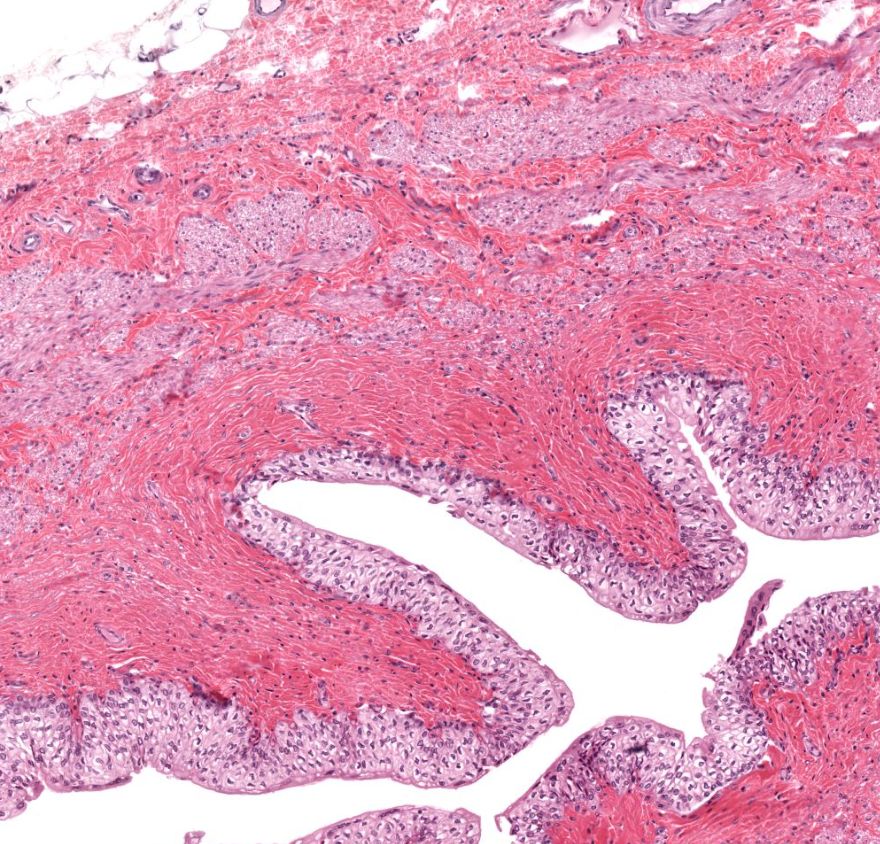

Trompa uterina

1: Trompa uterina - mucosa

2: Camada muscular - músculo liso